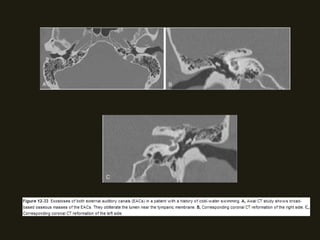

NEOPLASIAS BENIGNAS

OSTEOMAS E EXOSTOSES

• Tumores benignos mais comuns do osso temporal;

• Osteomas – surgem no processo mastóide, na bigorna e no

CAI;

• Exostoses – massas ósseas multinodulares de ambos os canais

auditivos externos; associação com exposição prolongada a

água fria (nadadores);

• TC – áreas de ossos densos;